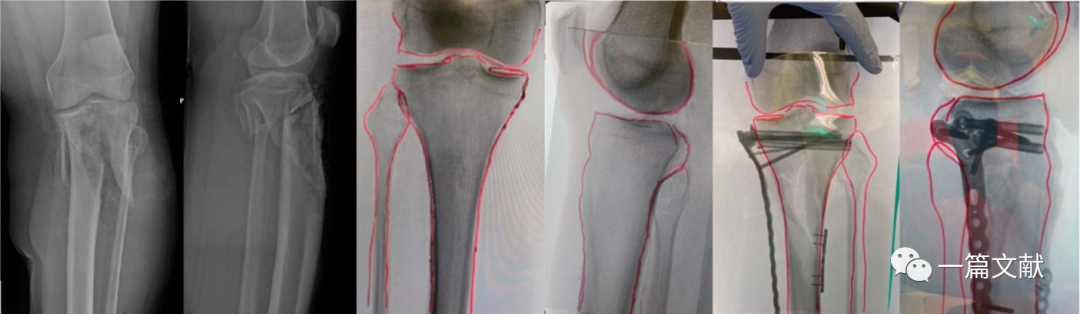

3、胫骨平台手术

对于累及双侧髁骨折,近端移位明显的骨折尤其有用,如下图: